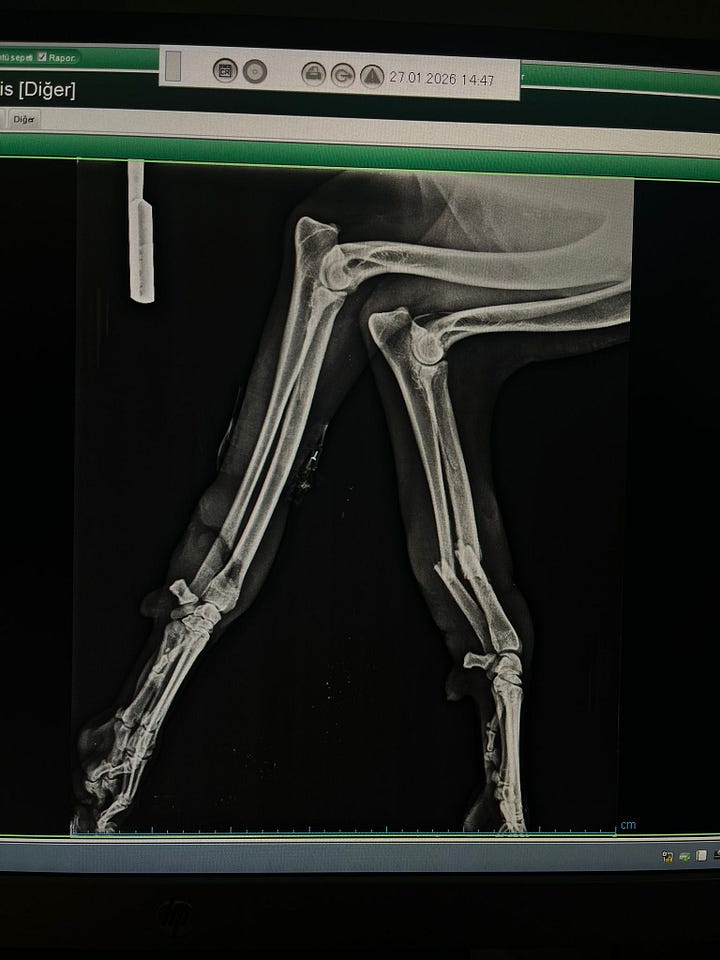

The body doesn’t wait patiently for medical help. It starts repairing immediately, even if things aren’t aligned properly. Scar tissue forms. Swelling builds. Early bone starts knitting together sometimes crooked, sometimes twisted, sometimes locked into completely the wrong position.

By the time a vet steps in weeks later, they’re not dealing with a clean break anymore. They’re dealing with the body’s rushed attempt to patch things up. And that makes surgery far more complicated.

Instead of simply stabilising the bone, the team often has to undo what’s already started healing, carefully realign everything, and then rebuild it properly.

For Atış, our vets chose to use a plate alongside an external fixator to hold everything steady while the bone heals.

If you’ve seen the video, you’ll know it looks a bit frightening at first glance. Metal bars and pins never look gentle. But it’s actually one of the best tools veterinary surgeons have. It stabilises the bone from the outside without putting extra stress on damaged tissue.